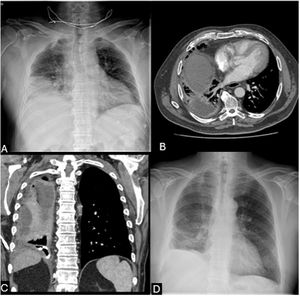

A 72-year-old male with chronic alcohol abuse, hypertension, dyslipidemia, and beta-lactam/streptomycin allergy presented with one week of fever, productive cough, and right-sided pleuritic pain. On admission, he manifested acute respiratory failure and chest X-ray revealed a right lower lobe consolidation (Fig. 1A).

(A) Chest X-ray showed a right lower lobe consolidation containing air foci and ipsilateral pleural effusion. (B) Chest CT scan showed a complex multiloculated pleural collection in the right hemithorax with septations and compressive atelectasis. (C) Coronal CT reconstruction confirming the loculated pleural collection in the right hemithorax. (D) Follow-up chest-X-ray at discharge documents complete resolution of pleural effusion, lung re-expansion and minimal residual basilar opacities in the right hemithorax.

Empirical levofloxacin therapy and high-flow oxygen support were initiated. Subsequent radiological deterioration (Fig. 1B and C) and ultrasound-guided thoracentesis yielded purulent pleural fluid, with matrix-assisted laser desorption/ionization-time of flight (MALDI-TOF) mass spectrometry identifying G. morbillorum. A pig-tail catheter drained 4800ml, but loculations required intrapleural urokinase and a second drainage, which isolated Prevotella oris, confirming polymicrobial infection.

Given the patient's allergy and polymicrobial suspicion, levofloxacin was replaced with intravenous clindamycin and vancomycin for 14 days. This regimen addressed both Gemella (vancomycin), polymicrobial anaerobes coverage and synergistic activity against Gemella (clindamycin) demonstrating this antibiotic regimen combination as an effective alternative for beta-lactam-allergic patients. Subsequent step-down therapy consisted of a 6-week course of oral clindamycin and azithromycin. Also, multidisciplinary management with repeated drainage and fibrinolytics was critical, reflecting the need for aggressive source control in complex empyema. The patient achieved full clinical and pleural effusion resolution confirmed at discharge (Fig. 1D).